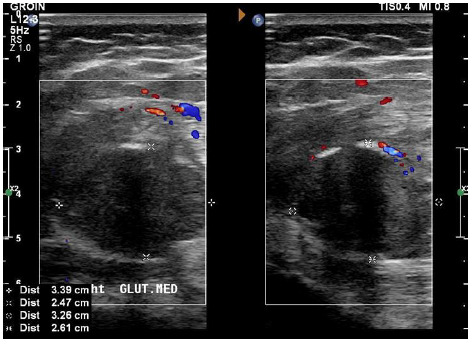

Findings: Palpation of the right buttock indicated a tender mass. Investigation by musculoskeletal ultrasound detected a large hypoechoic lesion. An MRI revealed patterns of calcification that were inconclusive in differentiating between a malignant or benign lesion. Macroscopic and microscopic histological examination, as well as immunohistochemistry, were consistent with myositis ossificans (MO), a non-malignant condition. The patient improved remarkably within three months of treatment with rest, non-steroidal anti-inflammatory drugs (NSAIDs) and extracorporeal shock wave therapy (ESWT).